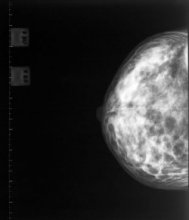

A new study has revealed the benefits of mammograms for women aged 75 years and older.

The research, published in the journal Radiology, shows that mammogram-detected breast cancers are found at an earlier stage; require less treatment; and lead to better survival rates.